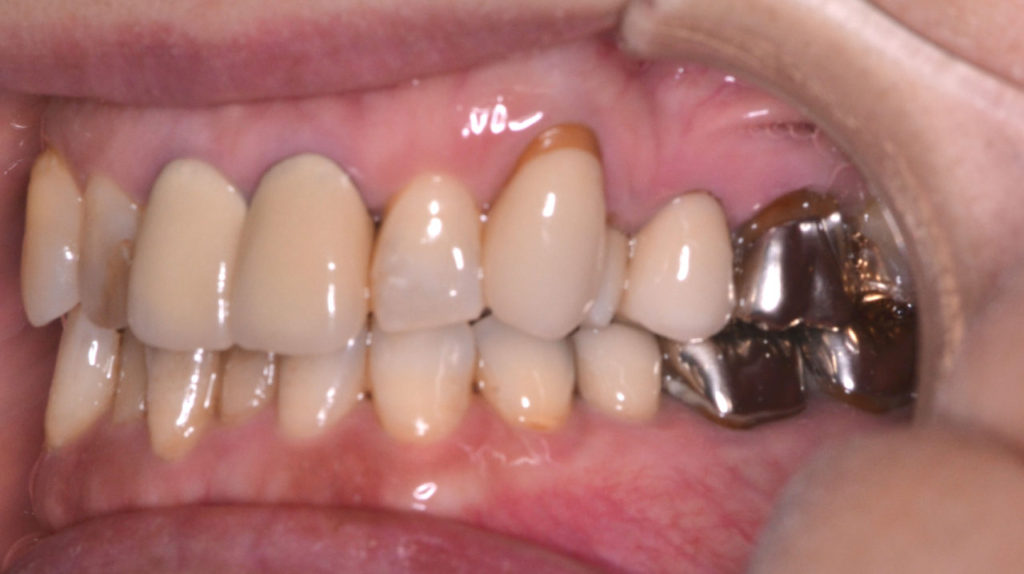

治療前

奥歯が干渉している状態